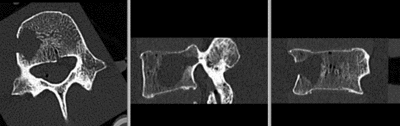

this is the main fixed reference image. All images are ev. aligned into this space lleft this is the moving image

baseline image follow-up

This dataset contains in vitro CT of two human vertibral body segments (L4) before and after regional damage. Goal is to align the two images to study in detail the local changes that occurred.

• fixed: CT , 0.342 x 0.342 x 0.20 mm voxel size, axial; 512 x 512 x 193 unsigned short image

• moving: CT , 0.342 x 0.342 x 0.20 mm voxel size, axial; 512 x 512 x 250 unsigned short image